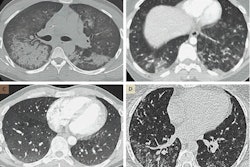

Axial reconstructed brain CT scans of patients with mild (A), moderate (B-D), or severe (E) hippocampal calcifications (indicated by arrows). Image courtesy of Dr. Pim de Jong, PhD.Hippocampal calcification